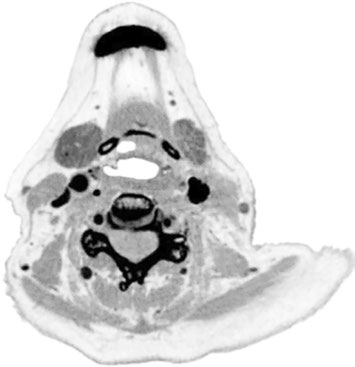

A practical example of this approach: a 79-year-old woman with T1N1 squamous cell carcinoma of the base of tongue had inadequate GTV visualization on single-contrast CT simulation (80 mL). The GTV was virtually indistinguishable from surrounding tissue. With double contrast (160 mL), the same patient had excellent tumor definition, allowing reliable delineation. This simple technique can enable SBRT at centers where simulation MRI is not routinely available.